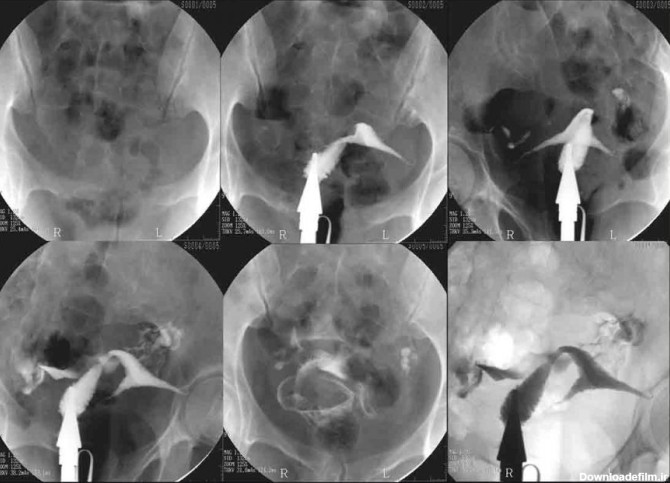

عکس رنگی رحم یا هیستروسالپینگوگرافی به معنای استفاده از اشعه ایکس برای مشاهده رحم و لولههای فالوپ است.

عکس رنگی رحم چیست؟ یک آزمایش اشعه ایکس که برای بررسی رحم و لوله های فالوپ و ناحیه اطراف آنها نگاه می کند و برای بررسی مشکلات ناباروری ممکن است انجام شود.

عکس رنگی رحم یا هیستروسالپنگوگرافی یکی از روش های تشخیصی شیوه ی تصویربرداری با اشعه ایکس است که معمولاً برای بررسی آناتومی رحم و لوله ها انجام میشود. عکس رحم

تصویربرداری رنگی رحم برای زنانی انجام می شود که دارای مشکلات باروری می باشند.یکی از رایج ترین مشکلات ناباروری ...